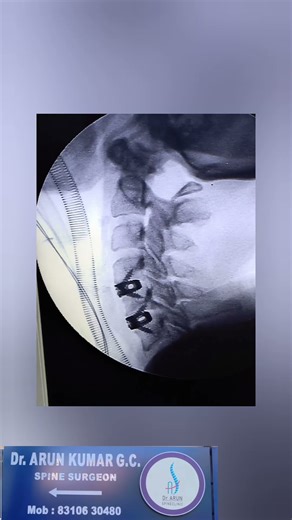

acdf surgery day 1 post op complete recovery

Arun Kumar G C spine

3 周前

Arun Kumar G C spine surgeon

1:30